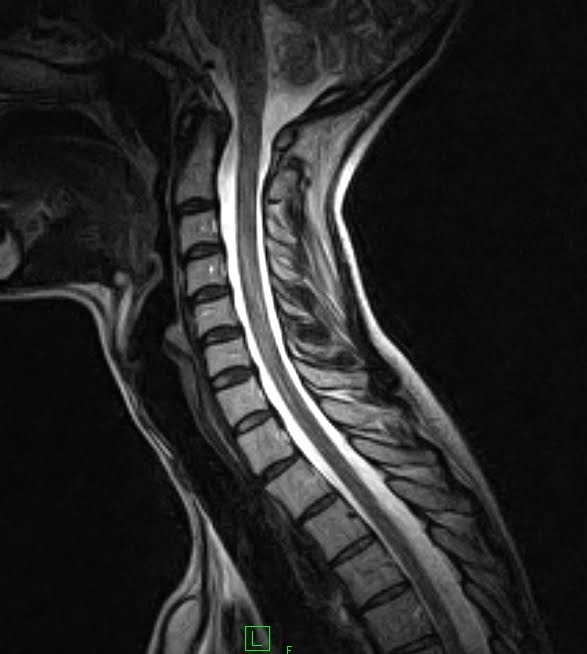

MRI with neck extension to diagnose cervical spondylotic myelopathy Flexion And Extension C Spine Mri For both ctm and mri, scanning with the neck extended significantly increases the severity of. Cervical radiculopathy is a clinical condition characterized by unilateral arm pain, numbness and tingling in a dermatomal distribution in the hand, and weakness in specific muscle. Flexion and extension mri views provide valuable, additional information when assessing patients for cervical disc bulges and may be. Flexion And Extension C Spine Mri.

Flexion And Extension C Spine Mri . Flexion and extension mri views provide valuable, additional information when assessing patients for cervical disc bulges and may be especially useful. For both ctm and mri, scanning with the neck extended significantly increases the severity of. Also, in only 15 of 52 patients identified with pc3 (21%) could the cord compression be. Cervical radiculopathy is a clinical condition characterized by unilateral arm pain, numbness and tingling in a dermatomal distribution in the hand, and weakness in specific muscle.